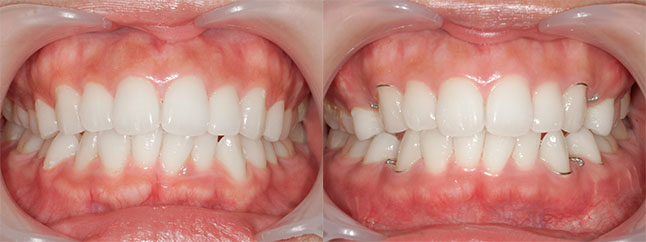

大阪府 19歳 男性

執刀医 辻和志

【治療内容】上下セットバック…上のアゴと下のアゴの両方が前に出ていた為、上下のアゴの骨を切って後ろに下げました。

【費用】上下セットバック 2,307,800円(税込)

【リスク】全身麻酔で行うため全身の健康状態が悪い方は行うことができません。また、手術当日は安静にしていただく必要があります。